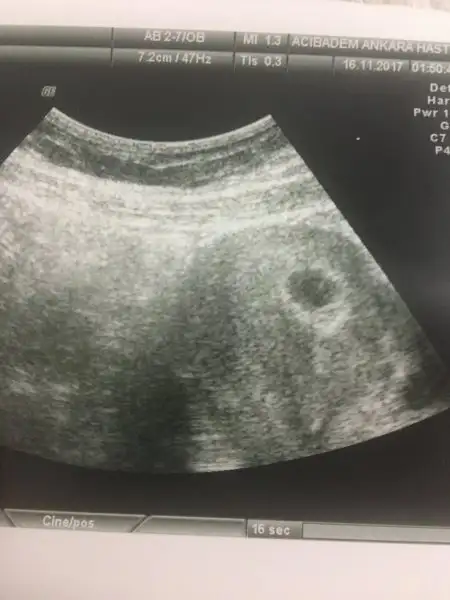

Canım kese şekli gayet iyi görünüyo ama bilemedim yolk sacı başka doktora gitsene canım yarın bi

Yolk sacı nedir bana hiç öyle bişeyden bahsetmedi göstermedi

Benim oglumda 6+5 te gorundu. Dr bos gebelik dedi yolk sac yok dedi kurtaj bile onerdi cok sukur gorduk sonunda.

Benim de bebek yolk hepsi gorundu ama kalp atisini duyamadik. Cumartesi doktor randevum var 6+3 olacagim insallah duyarim esim daha gormedi bebegi cok da heyecanli. Insallah babasi da geldi diye kalp atisini bize dinletir minik susamim